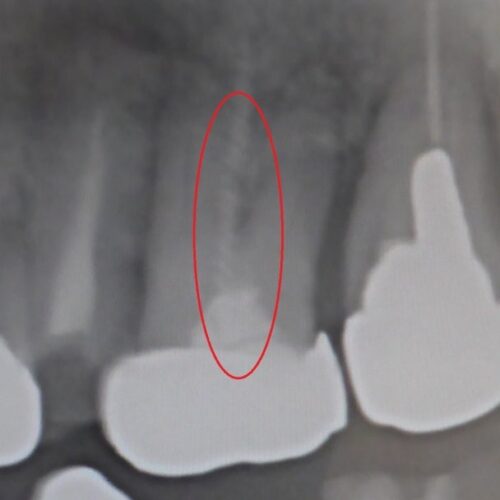

歯の中に折れた器具 発見

こんにちは 院長の亀井です。 今日は 根の治療のトラブルの1つを紹介 歯の中には神経が走っています。 虫歯が大きくなるな […]